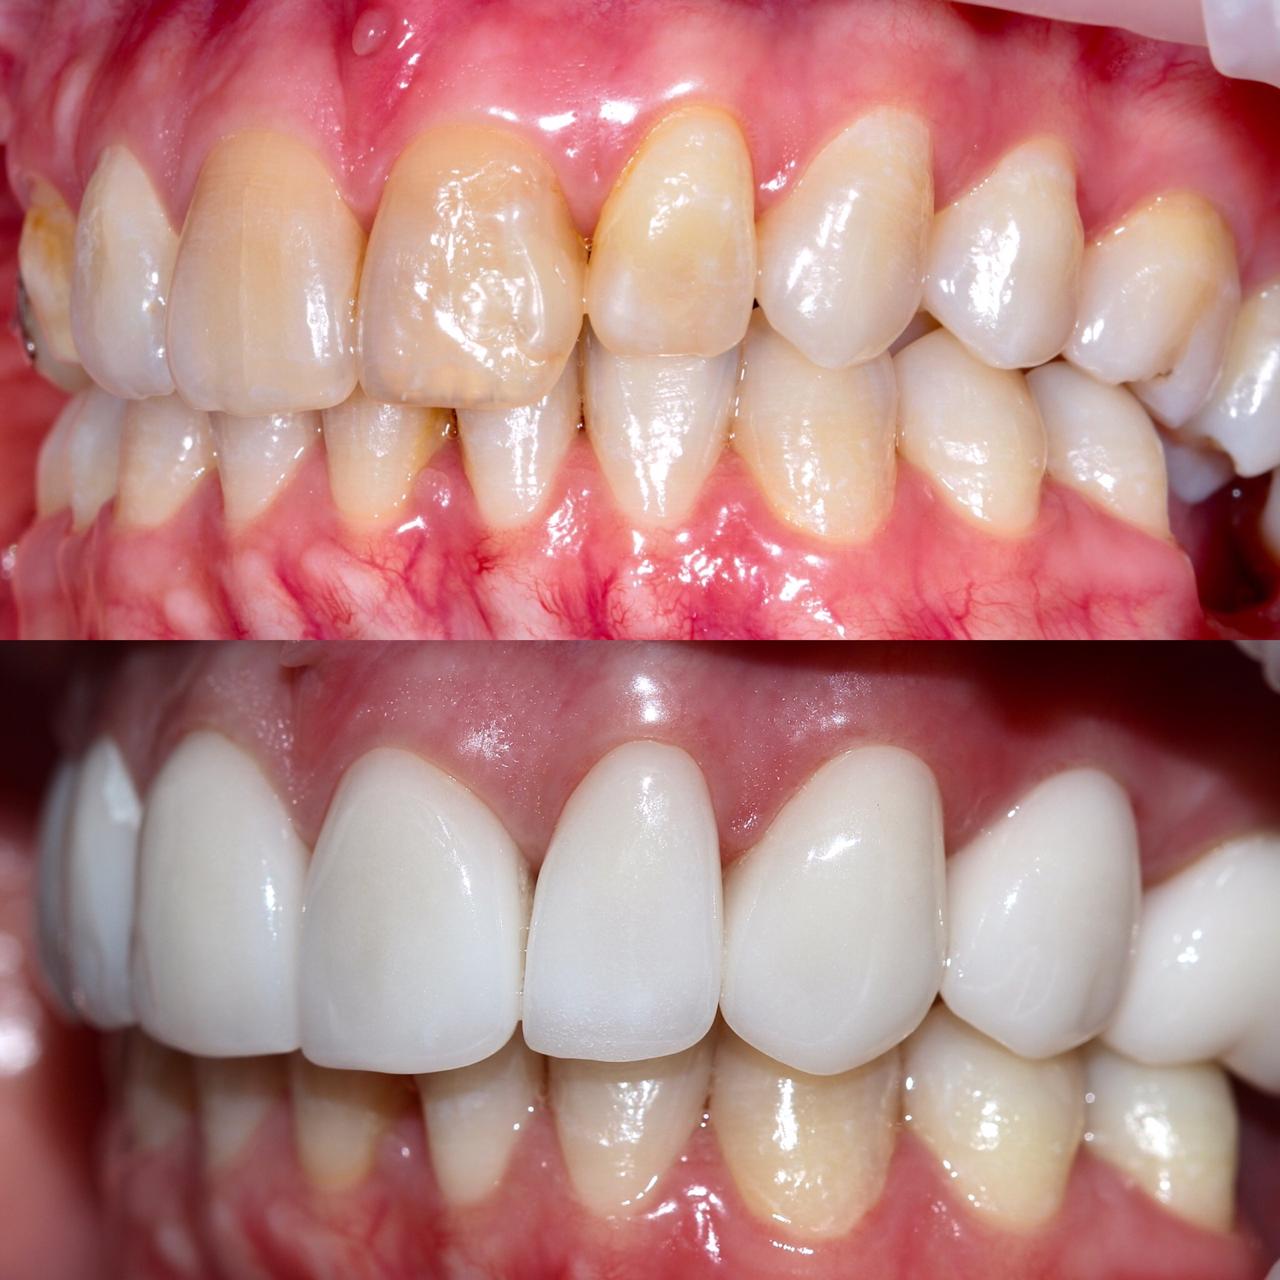

Примеры работ

Бережное и безболезненное лечение зубов